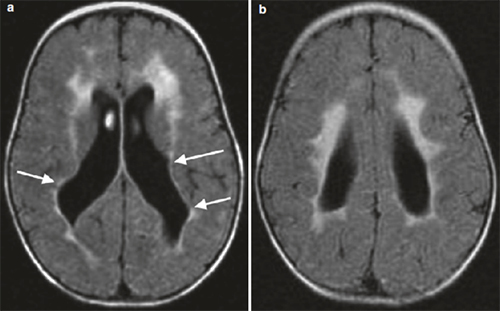

导致脑瘫的非进行性脑损伤病因,包括(1)发育不成熟的大脑(产前、产时或产后)、先天性发育缺陷(畸形、宫内感染) ;(2)获得性( 早产、低出生体重、窒息、缺氧缺血性脑病、核黄疸、外伤、感染);(3)脑瘫患儿出生时常常有早产或缺氧病史、以及感染、创伤等造成的脑损伤。常见的影像表现如下:

脑室周围白质脑病/脱髓鞘样改变

脑室出血造成脑组织梗塞